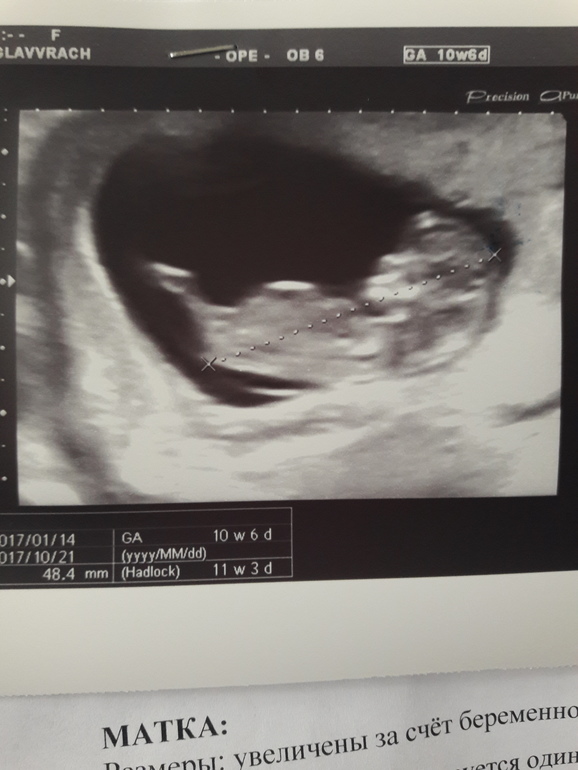

По итогам срок по месячным 10+6, а по узи 11+3 .

Размер ктр 48мм, ну и все остальные параметры тоже опережают. Ударов сердца 166. Врач так умилялась, когда ягодка моя потягушки делала. Сказала , что мы молодцы все отлично.

И только в этот раз мне поставили прикрепление плаценты (да она сказала , что уже полностью плацента) по передней стенке, да ещё и она и перекрывает зев :( не полностью, но все. Но подбодрила, что матка растёт и плацента будет подтягиваться вверх. На экране она показала где шейка, где плацента. У кого все поднялось в итоге???